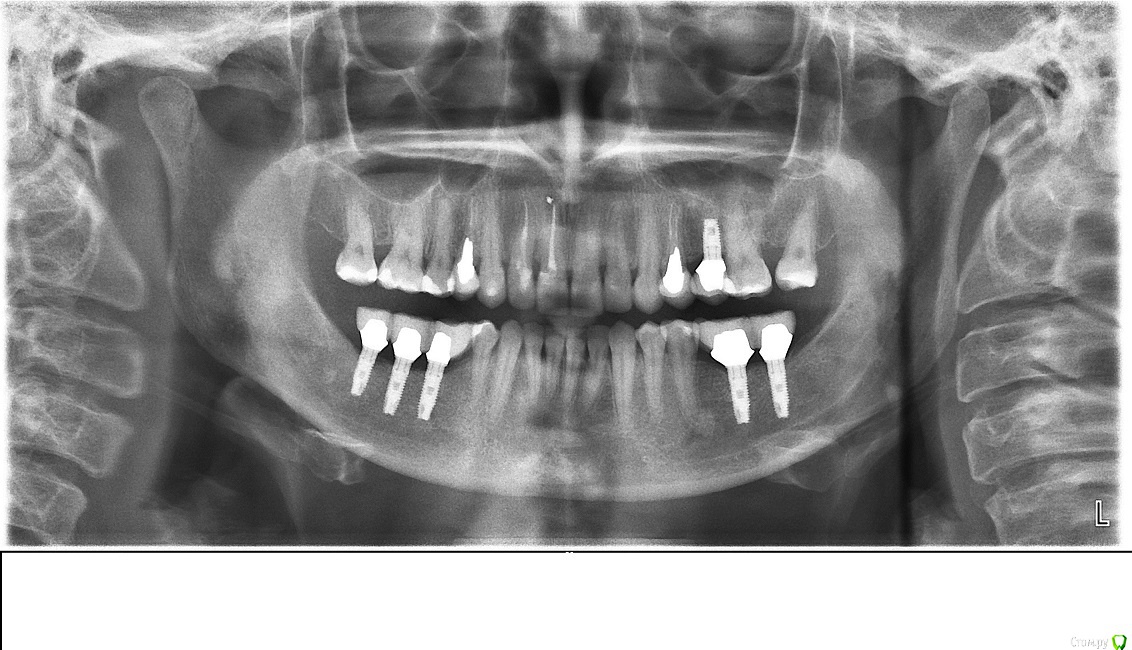

Таня-К Опубликовано 4 января, 2015 Поделиться Опубликовано 4 января, 2015 Добрый день! Проконсультируйте, пожалуста, по снимку. Два с половиной месяца назад закончено протезирование. На данный момент существует боль в области левого сустава (два-три раза в неделю, болит не сильно, что то между легкой болью и сильным дискомфортом). Мой врач несколько раз шлифовал контакты. Недавно я обратилась за консультацией в клинику, которая себя позиционирует как такая, что много внимания приделяет правильной окклюзии и на этом специализируется. Там мне сказали, что у меня большие проблемы с суставами (ассиметрия), это хроническое заболевание, "суставы назад вам никто не поставит", ортопедически эта проблема не решается, а только симптоматически. Посоветовали обратиться к остеопату.Уважаемые врачи! Буду очень благодарна за Ваше мнение по моей проблеме. Можно ли по этому снимку диагностировать (заподозрить) серьезные изменения в суставах? Или проблему можно решить (хотя бы частично) коррекцией коронок?Большое спасибо. Ссылка на комментарий

Skip Опубликовано 4 января, 2015 Поделиться Опубликовано 4 января, 2015 Можно ли по этому снимку диагностировать (заподозрить) серьезные изменения в суставах? "Заподозрить" то можно, но сказать что-то определённое нельзя, т.к. ОПТГ не является тем снимком, по которому ставят диагноз в отношении ВНЧС. МРТ наиболее информативный вид обследования. 1 Ссылка на комментарий